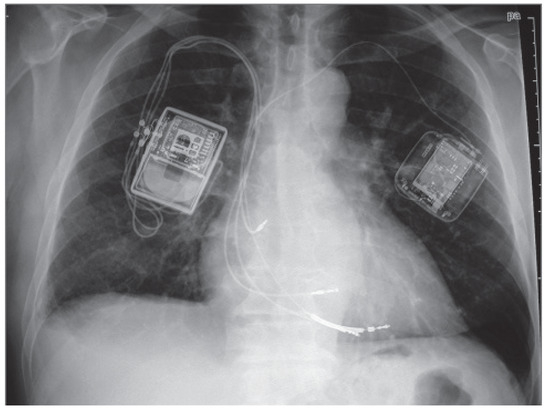

Changes in Ejection Fraction After an Ablate and Pace Procedure in Patients with Atrial Fibrillation

by Beat Schaer, Christian Sticherling, Heidi Abbühl, Michael Kühne and Stefan Osswald

Backround: “Ablate-and-pace” is an established procedure for selected patients with drug-refractory atrial fibrillation (AF). As consecutive right-ventricular pacing might have deleterious effects on left ventricular ejection fraction (LVEF), cardiac resynchronisation therapy (CRT) has been proposed as an alternative. Our aim was to evaluate [...] Read more.

Backround: “Ablate-and-pace” is an established procedure for selected patients with drug-refractory atrial fibrillation (AF). As consecutive right-ventricular pacing might have deleterious effects on left ventricular ejection fraction (LVEF), cardiac resynchronisation therapy (CRT) has been proposed as an alternative. Our aim was to evaluate the long-term follow-up of LVEF of such patients, to determine the rate of severe decline of LVEF and to find predictors. Methods: We included 27 patients with follow-up of >12 months and sufficient echocardiographic data for 65 ± 32 months. Last echocardiographic follow-up was performed after 61 ± 30 months. Main focuses were a decrease of LVEF to <35% and a decrease by >10%. Results: Mean LVEF at implant was 53% ± 9%. A LVEF of ≤40% (30%, 35% and 38%) was seen in three patients. At last follow-up, mean LVEF was 52% ± 8%. The three patients with a LVEF initially ≤40% improved (30% to 72%; 35% to 40%; 38% to 40%). LVEF changes in the three patients who at last follow-up had a LVEF of ≤40% were: 38% to 40%; 55% to 40%; 52% to 38%. In five patients (18%), LVEF decreased by ≥10%, though never to below 38%. The only predictors for a decrease in LVEF of ≥10% were lack of beta-blocker or angiotensin converting-enzyme inhibitor therapy at implant (p-values 0.02 and 0.003). Upgrade to CRT was performed in the patient with a LVEF of 38%. Conclusions: During long-term follow- up after “ablate-and-pace”, most patients with preserved or mildly impaired LVEF at implant do not exhibit a relevant decline in LVEF necessitating CRT upgrade. Full article